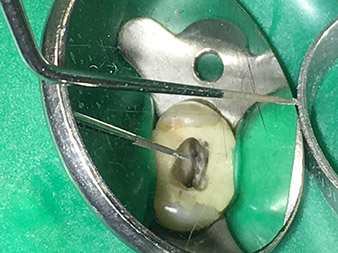

Dr. Nouraie: I have various favourite tips, but my absolute favourite tip and the one I couldn’t be without is the 1E tip. It really is useful in every single root canal treatment, as it can be used to activate the rinsing fluid. It is well known that, alongside the preparation, rinsing of the root canal is the most important component of the treatment. Activated rinsing fluid penetrates deeper into the dentinal tubules, thereby achieving better results. As such, activation of the rinsing fluid plays an important role in improving the quality of this type of treatment.

The 6E/3E and 4E tips are also some of my absolute favourites, but the indications for those are somewhat more strictly delineated. They are not necessarily always required for broad canals with one root, but are almost always used for teeth with multiple canals. Possible applications include removal of dentine overhangs from cavities, perfect rounding off of transitions and making thin canals and openings visible. However, caution should be exercised, as steps may be formed.

Dr. Nouraie: The use of ultrasonic tips allows targeted, atraumatic, minimal removal of substance at the desired site (e.g., when exposing the canal openings, rounding off the cavity floor and exposing broken-off instruments or posts as well as when processing coronal canal sections).

Canal transitions can be smoothed and rounded off with more precision than when using burs. The activation of the rinsing fluid in particular offers enormous advantages that cannot be guaranteed with other instruments. The special instruments from W&H make it possible to perform completely new indications minimally invasively such as revision of broken-off tips and posts.

Dr. Nouraie: For me, ultrasonic endodontics is an optimal complement to the techniques previously available. Use of the expanded W&H endo tip range makes it possible to improve the quality of the treatment and thus the long-term prognosis for the teeth substantially. The quality of the tips is exceptionally high and absolutely worth recommending.

I find the abrasion performance particularly impressive, as it remains constant even after frequent use. In addition, the instruments can also be reprocessed very simply and cost-effectively.